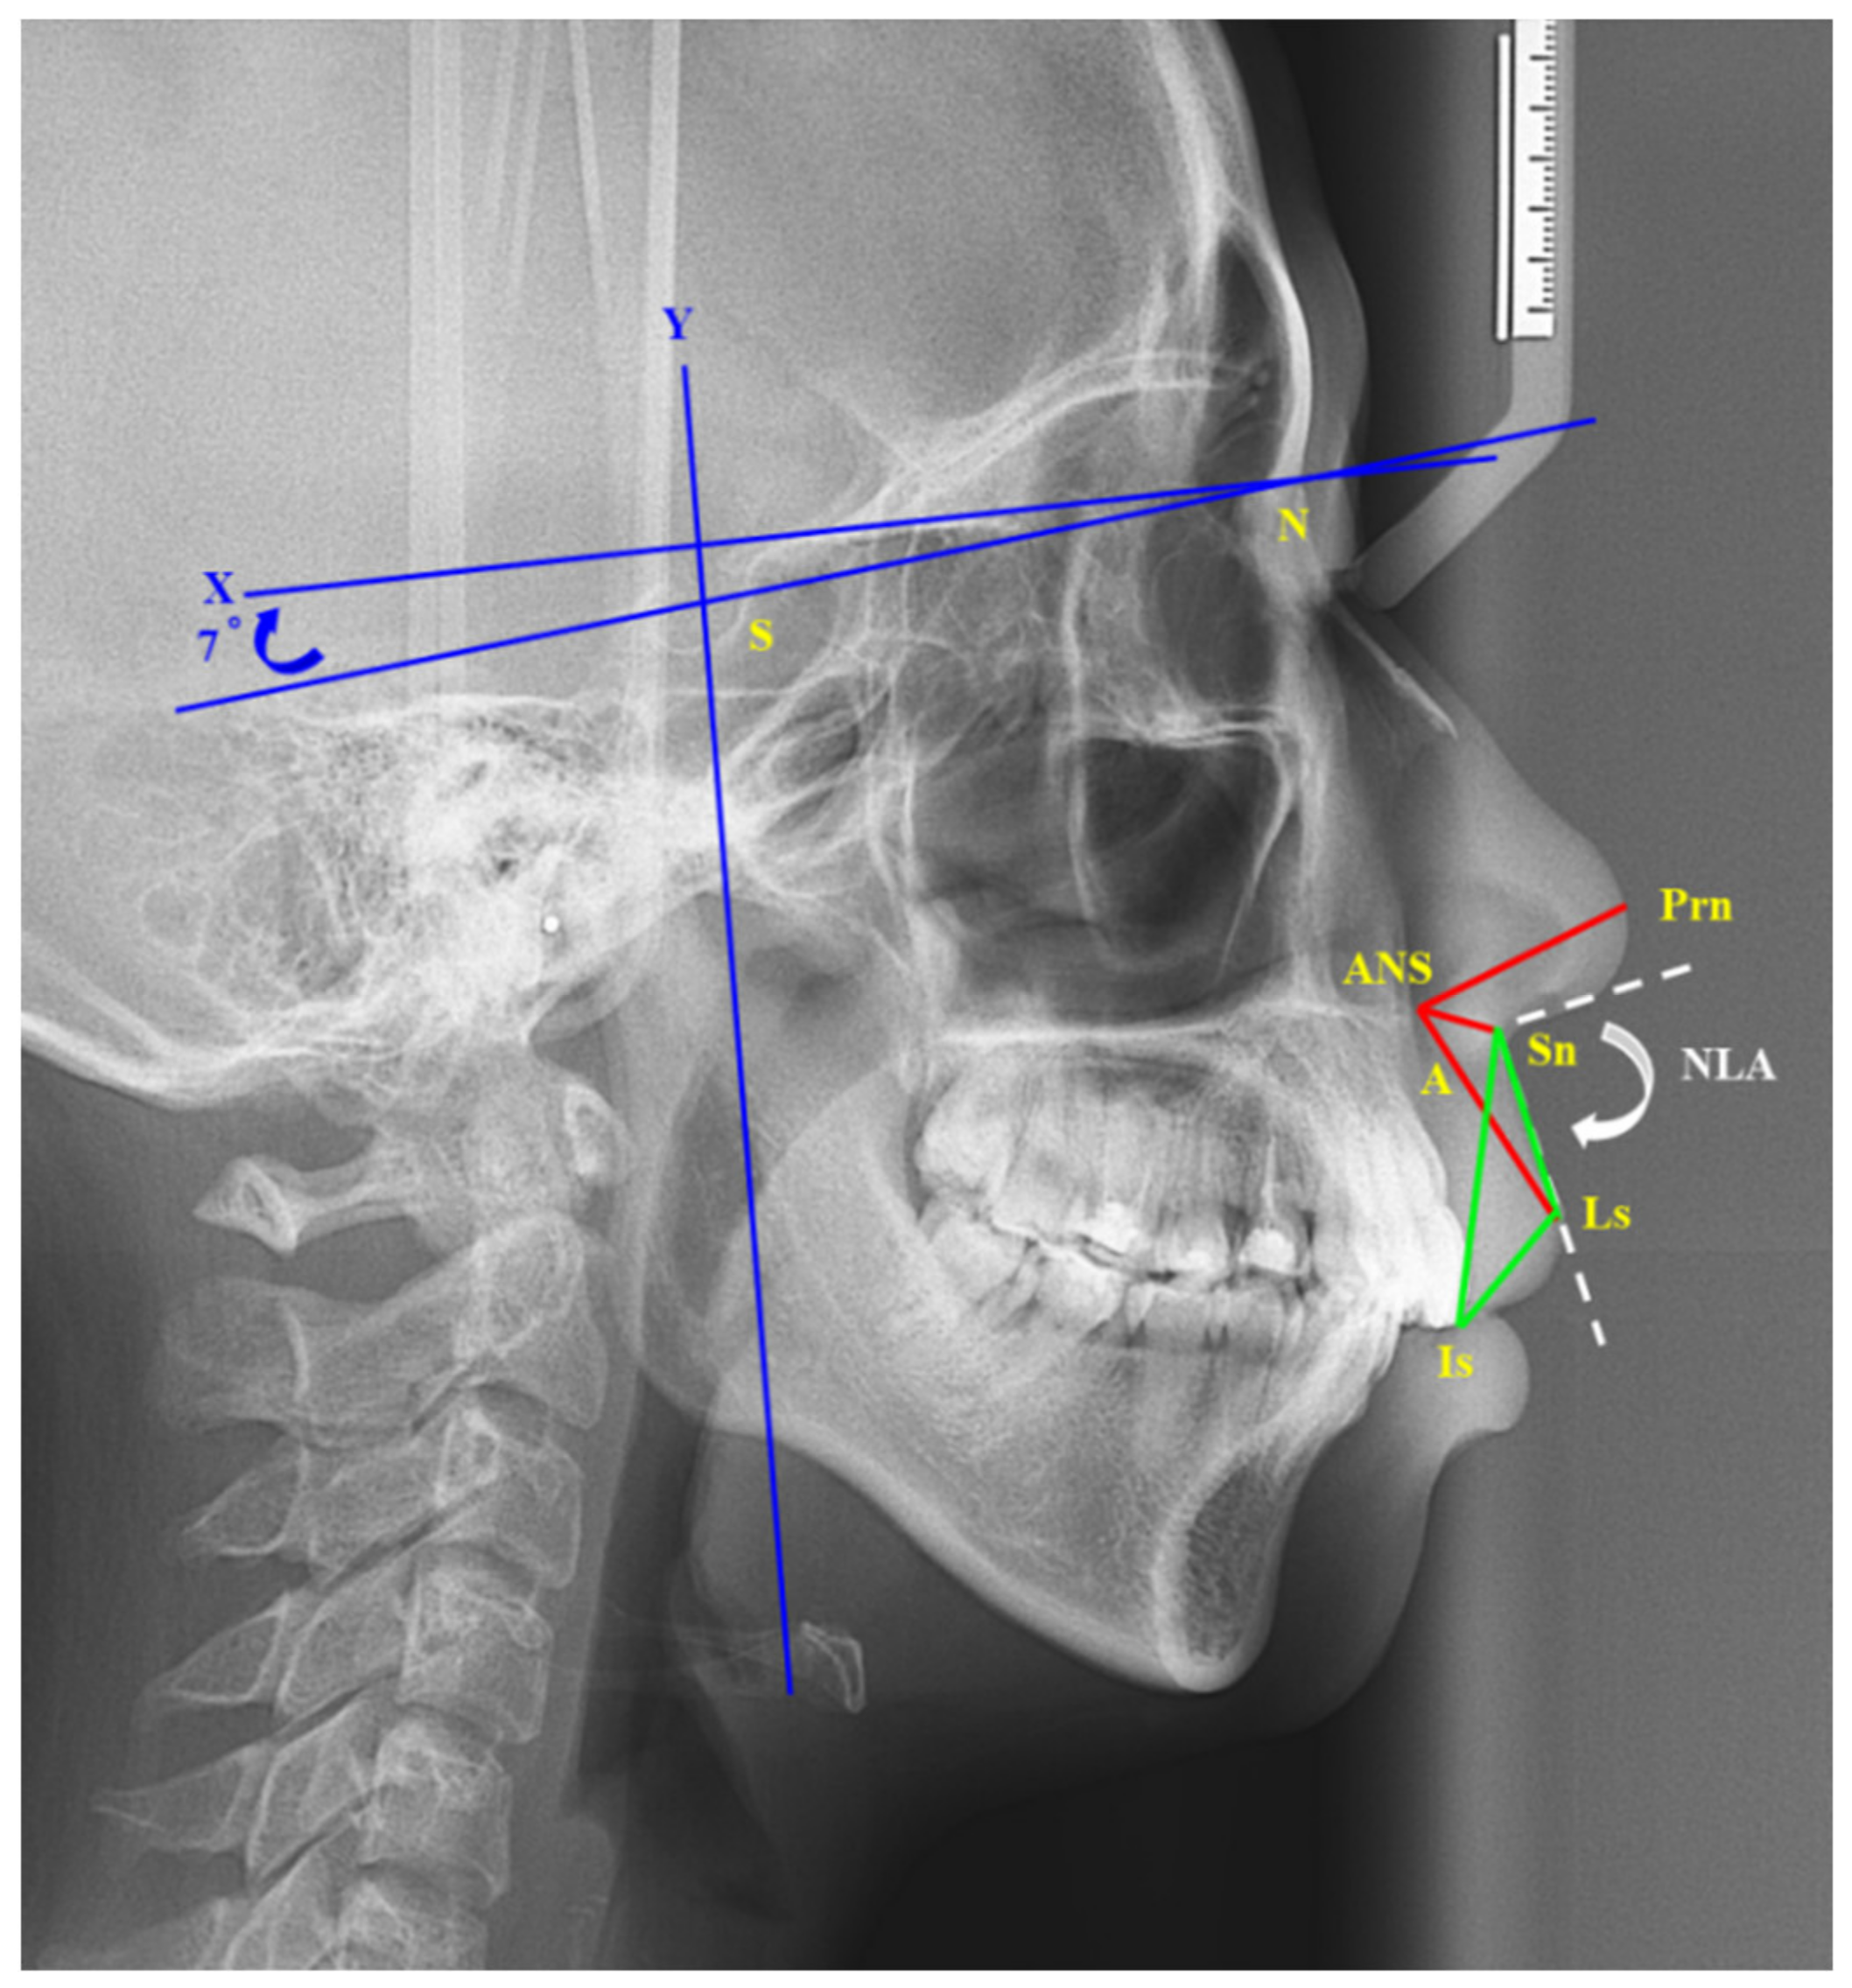

Wondering what to expect regarding your face before and after sinus surgery? Discover how functional endoscopic sinus surgery (FESS) impacts facial appearance, reduces chronic congestion, and alleviates inflammation. Explore recovery timelines, potential swelling, and physical changes to your nasal structure, ensuring you are fully prepared for the transformative health benefits of this common ENT procedure.

Read full article: Face Before And After Sinus Surgery